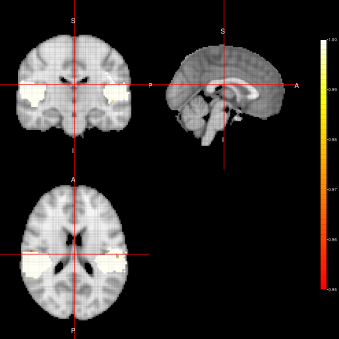

Marginal-FFBS Joint-FFBS

Refer to caption Refer to caption

ACE-FFBS

Refer to caption

Figure 3: Activation Maps for the ”voice localizer” example obtained when using the FFBS algorithm under three different distributions (Marginal, Joint and LTT) related to the state parameter.

From figures 2, 3 and 4, we can see the activation maps obtained for the ”voice localizer” experiment using the method proposed in this work. From those images, we can say that the three algorithms (FEST, FFBS and FSTS) under the three different distributions (Marginal, joint and LTT or average distribution) successfully identify the temporal activation due to voice and non-voice sounds stimulation, nevertheless there are some slight differences among those maps worth mentioning. For instance, the maps obtained when using the FFBS algortihm allows for the identification of a broader activated region from the temporal cortex, however, on the other hand, it allows activations to appear (false-positive activations) on brain regions that should not be involved with this ”voice localizer” experiment. On the other hand, more conservative results seem to be obtained when using FEST and FSTS algorithms, but with less false activations.